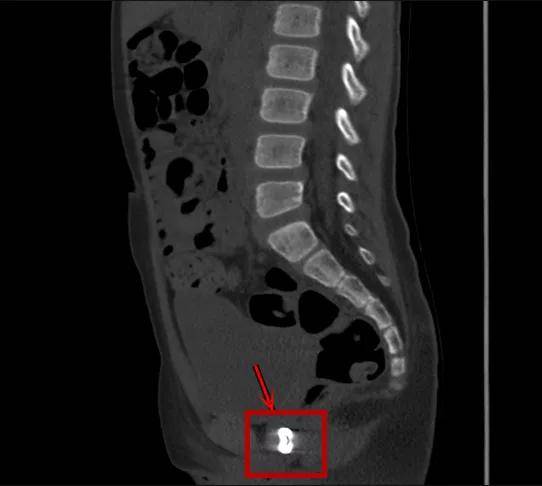

还有些异物的位置令人匪夷所思

8岁·阴道异物

纽扣

半天前患儿反复诉会阴部疼痛,自诉经阴道塞入异物,家长说是可能是纽扣。